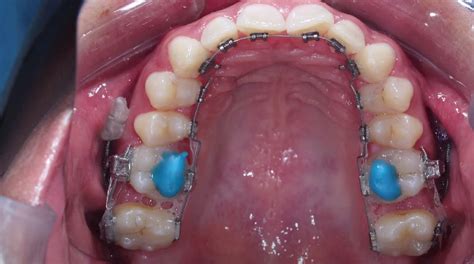

- Región anterior: Levante efectuado en las caras palatinas de los incisivos centrales superiores.

- Región posterior: Levante realizado en la cara oclusal de los molares y premolares.

El composite es el material más comúnmente utilizado. Este material es conocido por su durabilidad y fácil manipulación. Se emplea para crear tanto levantes de mordida prefabricados como personalizados.

Otra opción popular es la resina fotopolimerizable. Este material se usa particularmente en levantes posteriores y tiene la ventaja de liberar flúor, lo que brinda protección adicional a los dientes.

El levante de mordida posterior es una técnica precisa recomendada por el ortodoncista para asegurar la alineación dental correcta y prevenir complicaciones antes de la colocación de los brackets.

En pacientes con overjet aumentado, se sugiere colocar el ajuste en los caninos para brindar un mejor soporte. Para corregir mordidas irregulares, se puede aplicar el ajuste uniendo los dientes anteriores de canino a canino, lo que ayuda a prevenir la formación de espacios entre los dientes.